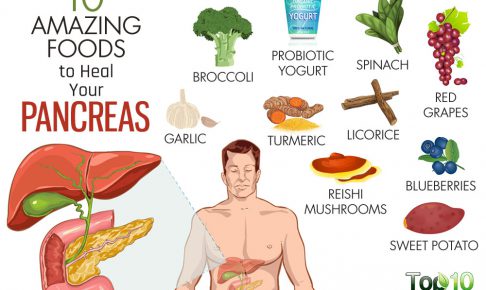

臓器

臓器

臓器

臓器

臓器

臓器

臓器

臓器

臓器

臓器

臓器

臓器

臓器

臓器

臓器

臓器